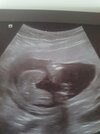

Hej dziewczyny jestem po wizycie usg polowkowym 19 tydz .. No i lekarza wypowiedz Prawdopodobnie dziewczyna bedzie bo,, nic tu nie dynda,, ale nie mowi ze nie wyjdzie z tego chlopiec tylko na dzien dzisiejszy powinno na chlopcaa cos dyndac miedy nogami tu nie dynda więc wniosek ze bedzie chyba Martynka 🤷🏼‍♀😁 co myslicie?

• 20220621_150730.jpg

20220621_150730.jpg

1,2 MB · Wyświetleń: 168